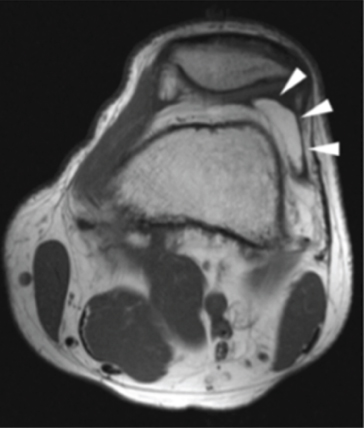

Simple radiographs showed no abnormal findings, and MRI images revealed a soft tissue mass located superolaterally to the PF joint that exhibited an ill-defined border with its surroundings. Both T1- and T2-weighted images at high signal intensities revealed the soft tissue mass, while low signal intensity was noted under fat suppression and no contrast enhancement was noted under contrast imaging (Figure 1). In addition, there were no abnormal findings in the blood examination.